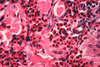

What are the molecular and morphologic changes of the image? ( MDx)

Clinical history and signs: 3 week old puppy, anorexia, dypsnea, abd pain upon palpation, normal rectal temperature

Multifocal, acute renal necrosis and hemorrhage or necrohemorrhagic nephritis

What is the etiology?

Clinical history and signs: 3 week old puppy, anorexia, dypsnea, abd pain upon palpation, normal rectal temperature

Canine herpesvirus-1 (CHV-1)

- red spots are from the virus targeting endothelium

What is the pathogenesis?

Clinical history and signs: 3 week old puppy, anorexia, dypsnea, abd pain upon palpation, normal rectal temperature

Transmission CHV-1 to pup at birth >incubation period of up to 1 week > virus replicates at temperature lower than 37C (98.6F) > endothelial cell tropism > multifocal necrosis in numerous organs